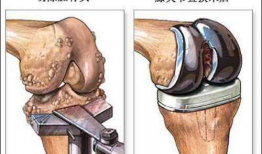

膝关节置换手术视频,从术前准备到术后康复

你有没有想过,当你的膝关节像老化的弹簧一样“嘎吱嘎吱”作响时,会有一种神奇的手术能把它换成一个全新的呢?没错,就是膝关节置换手术...